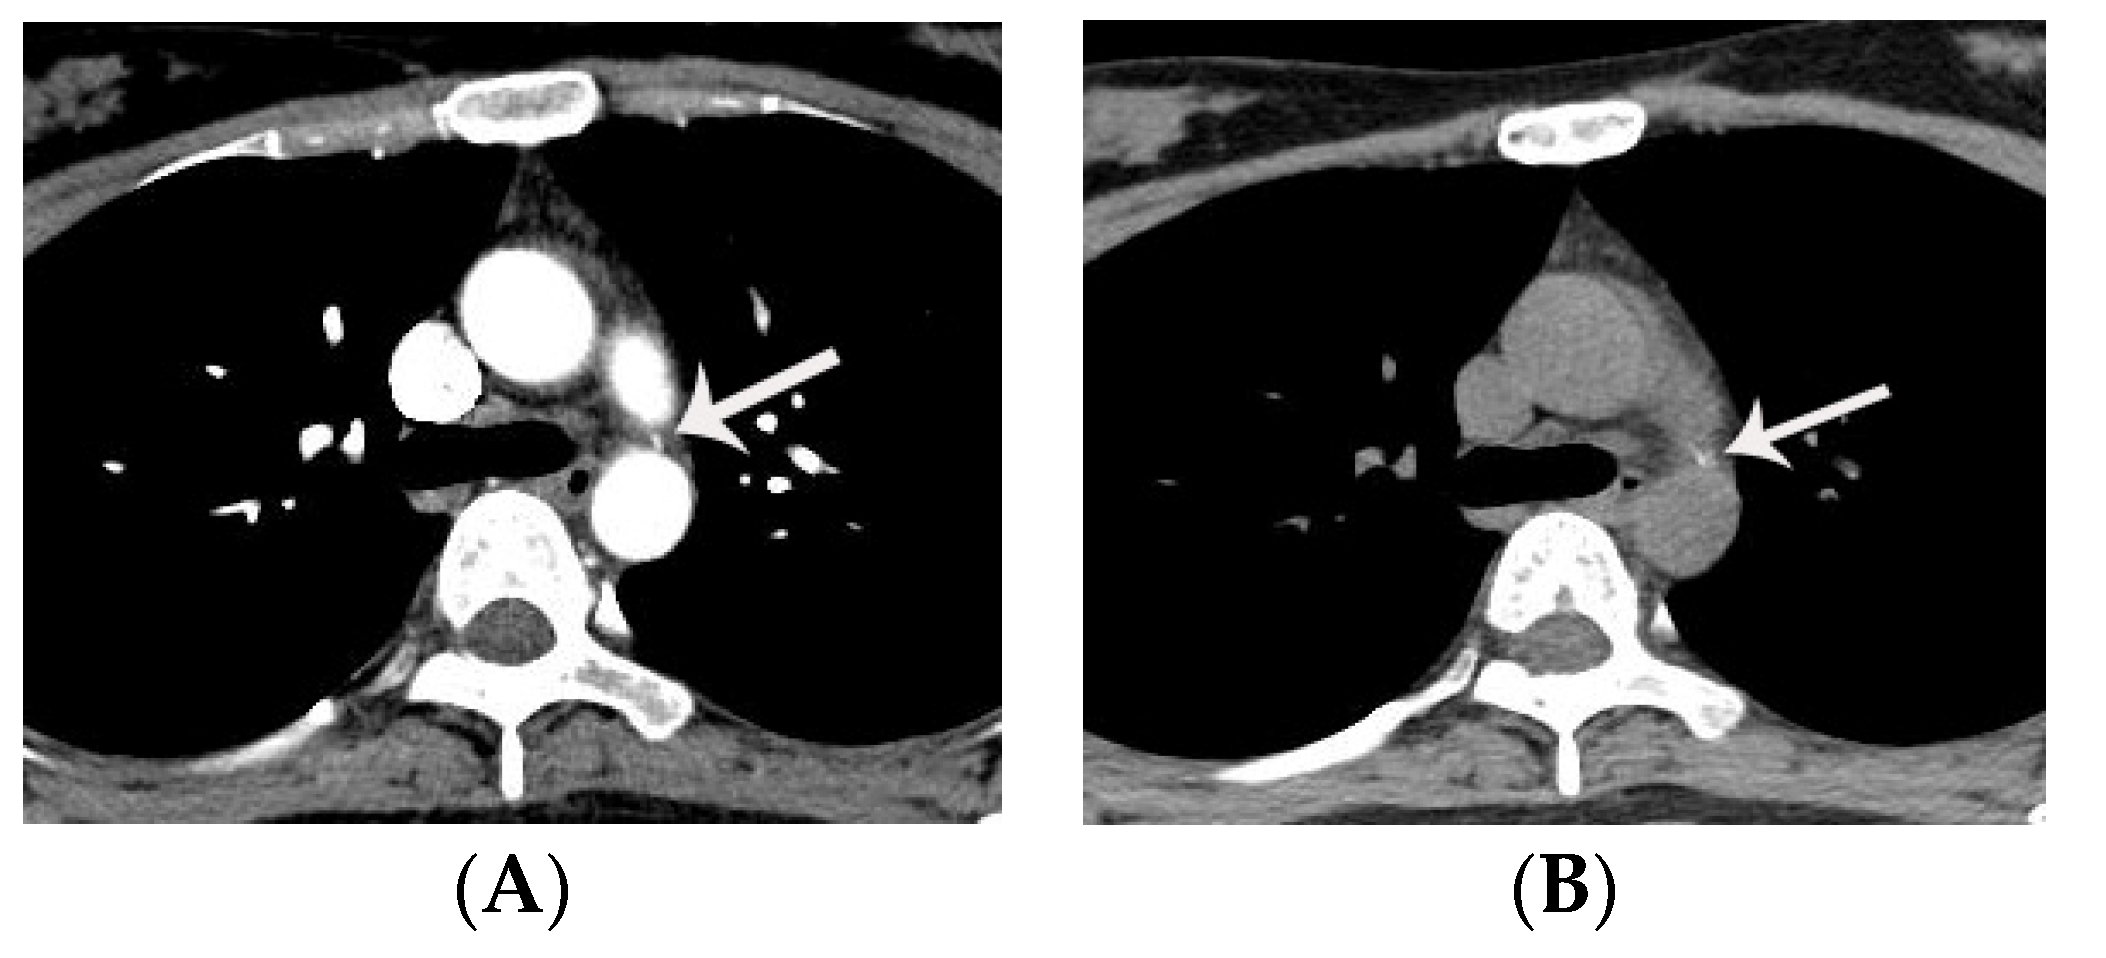

7. Diagnostic Pitfalls of PDA on Chest CT

- Son, M.J.; Chun, E.J.; Yoo, S.M.; Lee, H.Y.; Song, I.S.; White, C.S. High prevalence of a linear valve-like structure on CT at the pulmonary artery terminus of patent ductus arteriosus in adult patients, mimicking endarteritis. Surg. Radiol. Anat. 2021, 43, 317–321. [Google Scholar] [CrossRef] [PubMed]

- Lee, D.; Yoo, S.M.; Lee, H.Y.; White, C.S. Computed Tomography Diagnosis of Patent Ductus Arteriosus Endarteritis and Septic Pulmonary Embolism. Korean Circ. J. 2020, 50, 182–183. [Google Scholar] [CrossRef]